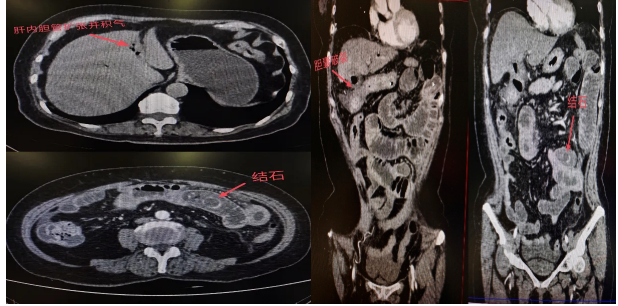

随后腹部 CT 检查结果显示:李阿姨的胆囊已经发生穿孔,一枚结石从破口处掉进小肠,并牢牢卡在肠腔内,形成了机械性肠梗阻。 更严重的是,由于结石嵌顿时间较长,已导致局部肠壁明显水肿、炎症。

12 月 16 日,周亮主任为李阿姨施行了小肠切开取石术 。手术中,周亮主任在李阿姨的小肠内共取出三枚结石,最大的一枚直径约 5 厘米,类似于鸡蛋形状。